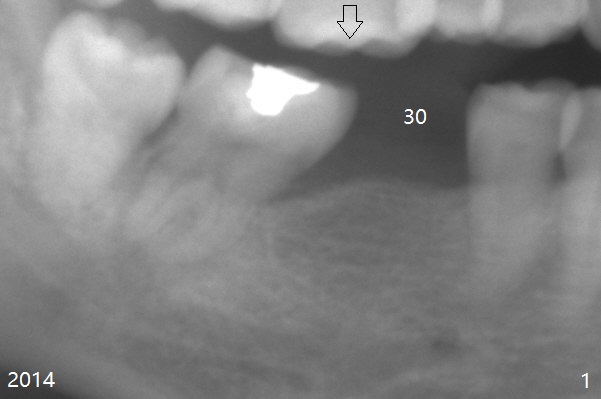

A 49-year-old man requests implants because of difficulty in eating. The teeth #19 and 30 are missing, while #18 and 31 have mobility. For the sake of dental insurance, an implant will be placed at #30 first. Due to long standing edentulism with opposing supraeruption (Fig.1 arrow), the ridge must be narrow. After ridge reduction, the bone height will be ~ 10 mm (Fig.2). To prevent screw loosening, a 1-piece implant will be used. To compensate for height limitation, the diameter of the implant will be 3.5 or 4.0 mm. If the restorative height is favorable, fabricate a provisional prior to suturing so that subgingival margin is possible (to improve cosmetics and prevention of food impaction). If the vertical height is limited for provisional, create clearance barely enough for periodontal dressing. Overprep of abutment height in the early stage may be related to easy dislodgement of the crown later on.